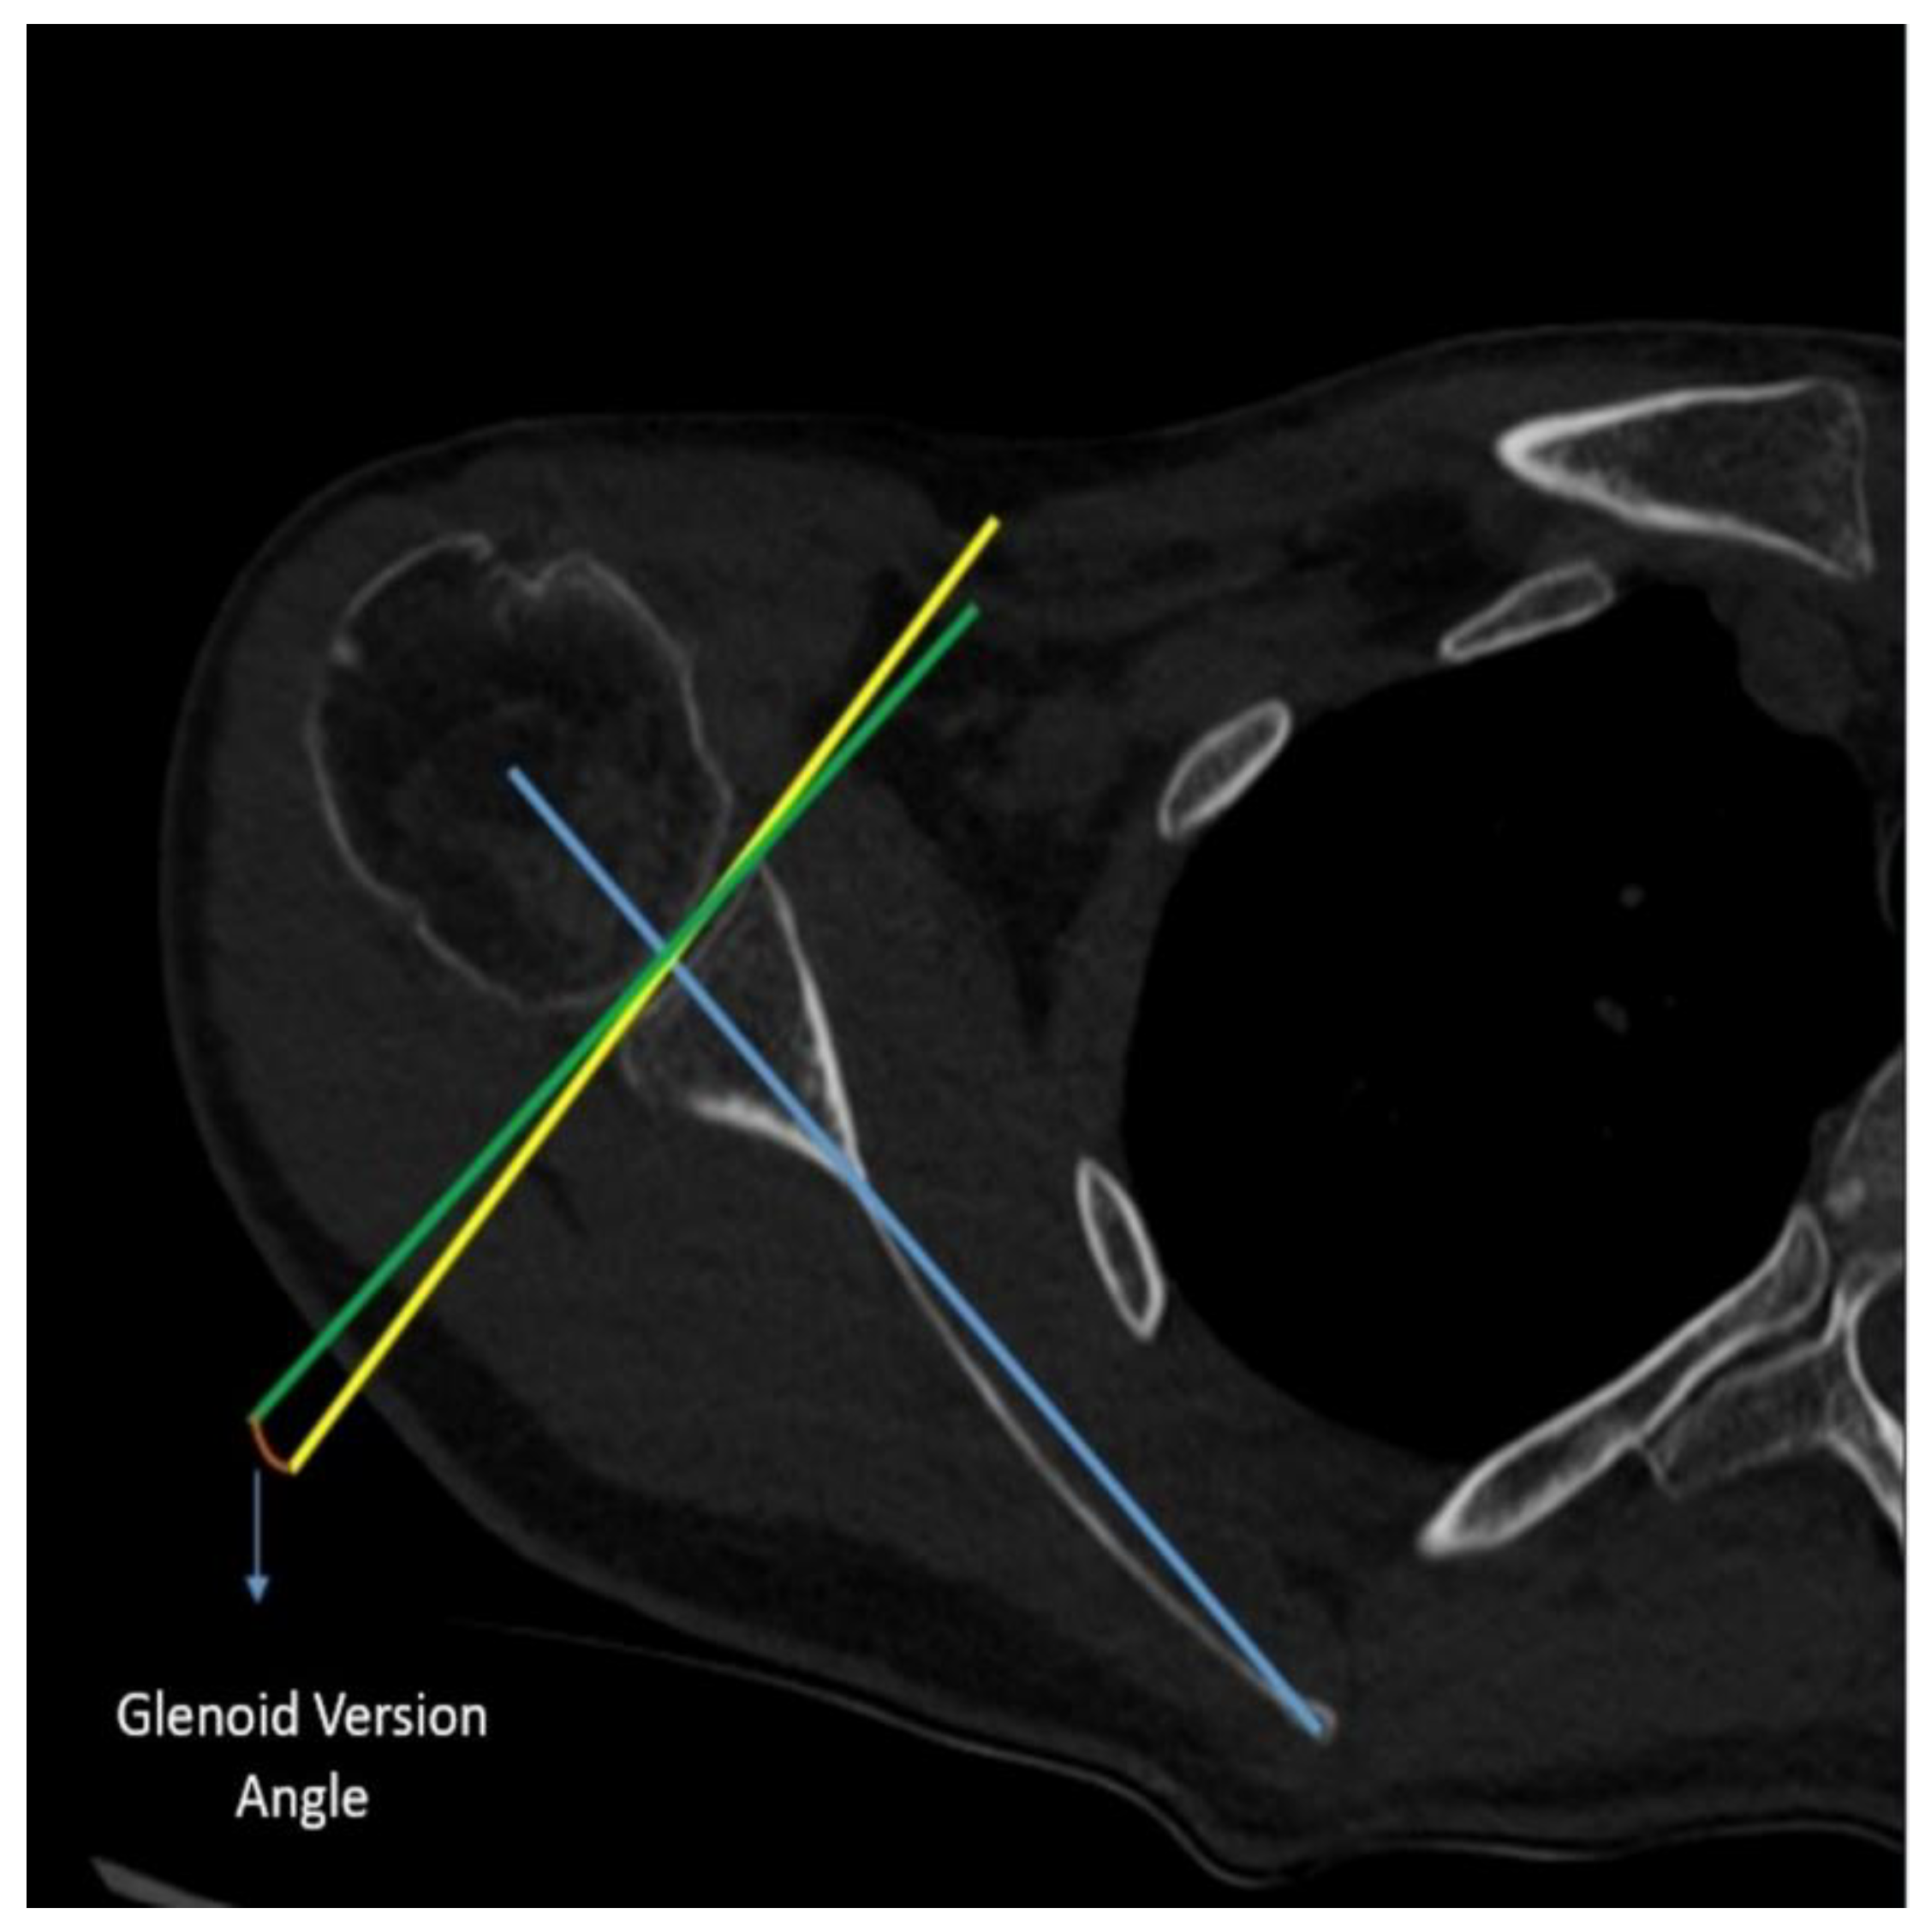

Purpose: This study aimed to determine the relationship between alpha angle (the angle between the screws and the glenoid) and thoracic diameters in patients undergoing the Latarjet procedure. Defining the relationship between thoracic morphology and alpha angle is aimed to fill the gap in the literature to improve surgical outcomes. Methods: This retrospective study analyzed 74 patients who underwent the Latarjet procedure for recurrent anterior shoulder instability between 2022 and 2024. All procedures were performed by the same surgeon using a standardized protocol to ensure consistency of surgical technique across cases. In postoperative chest CT scans, alpha angle, anteroposterior diameter of the thorax, transverse diameter of hemithorax, scapular inclination, and glenoid version were evaluated. Results: The study included predominantly male patients (90%) with a mean age of 26.4±6.4 years who underwent Latarjet procedures predominantly on the right side (60%). Significant associations were observed between thoracic morphology and alpha angle on postoperative CT scans. There was a significant positive correlation between anterior-posterior/transverse diameter ratio (AP/T) and alpha angle (r=0.407, p<0.001), as well as correlations between scapular inclination, glenoid version, thoracoscapular angle, and alpha angle (r=0.275, p=0.018; r=0.241, p=0.039; r= -0.288, p=0.013, respectively). Patients were divided based on an alpha angle threshold of 15 degrees, with results indicating worse outcomes for angles above this threshold. Additionally, the AP/T ratio demonstrated predictive value for poor outcomes (AUC=0.660, p=0.018) with a threshold of 1.2545. Conclusion: This study highlights the direct impact of thoracic morphology on the alpha angle observed on post-Latarjet chest CT scans. Specifically, patients with a higher ratio of anterior-posterior to transverse thoracic diameter (AP/T) show a proportional increase in alpha angle. When the AP/T ratio exceeds 1.25, surgeons may face challenges in achieving the target alpha angle.

| Glenoid Version | -1.57 ± 5.64 | 0.97 ± 4.78 |